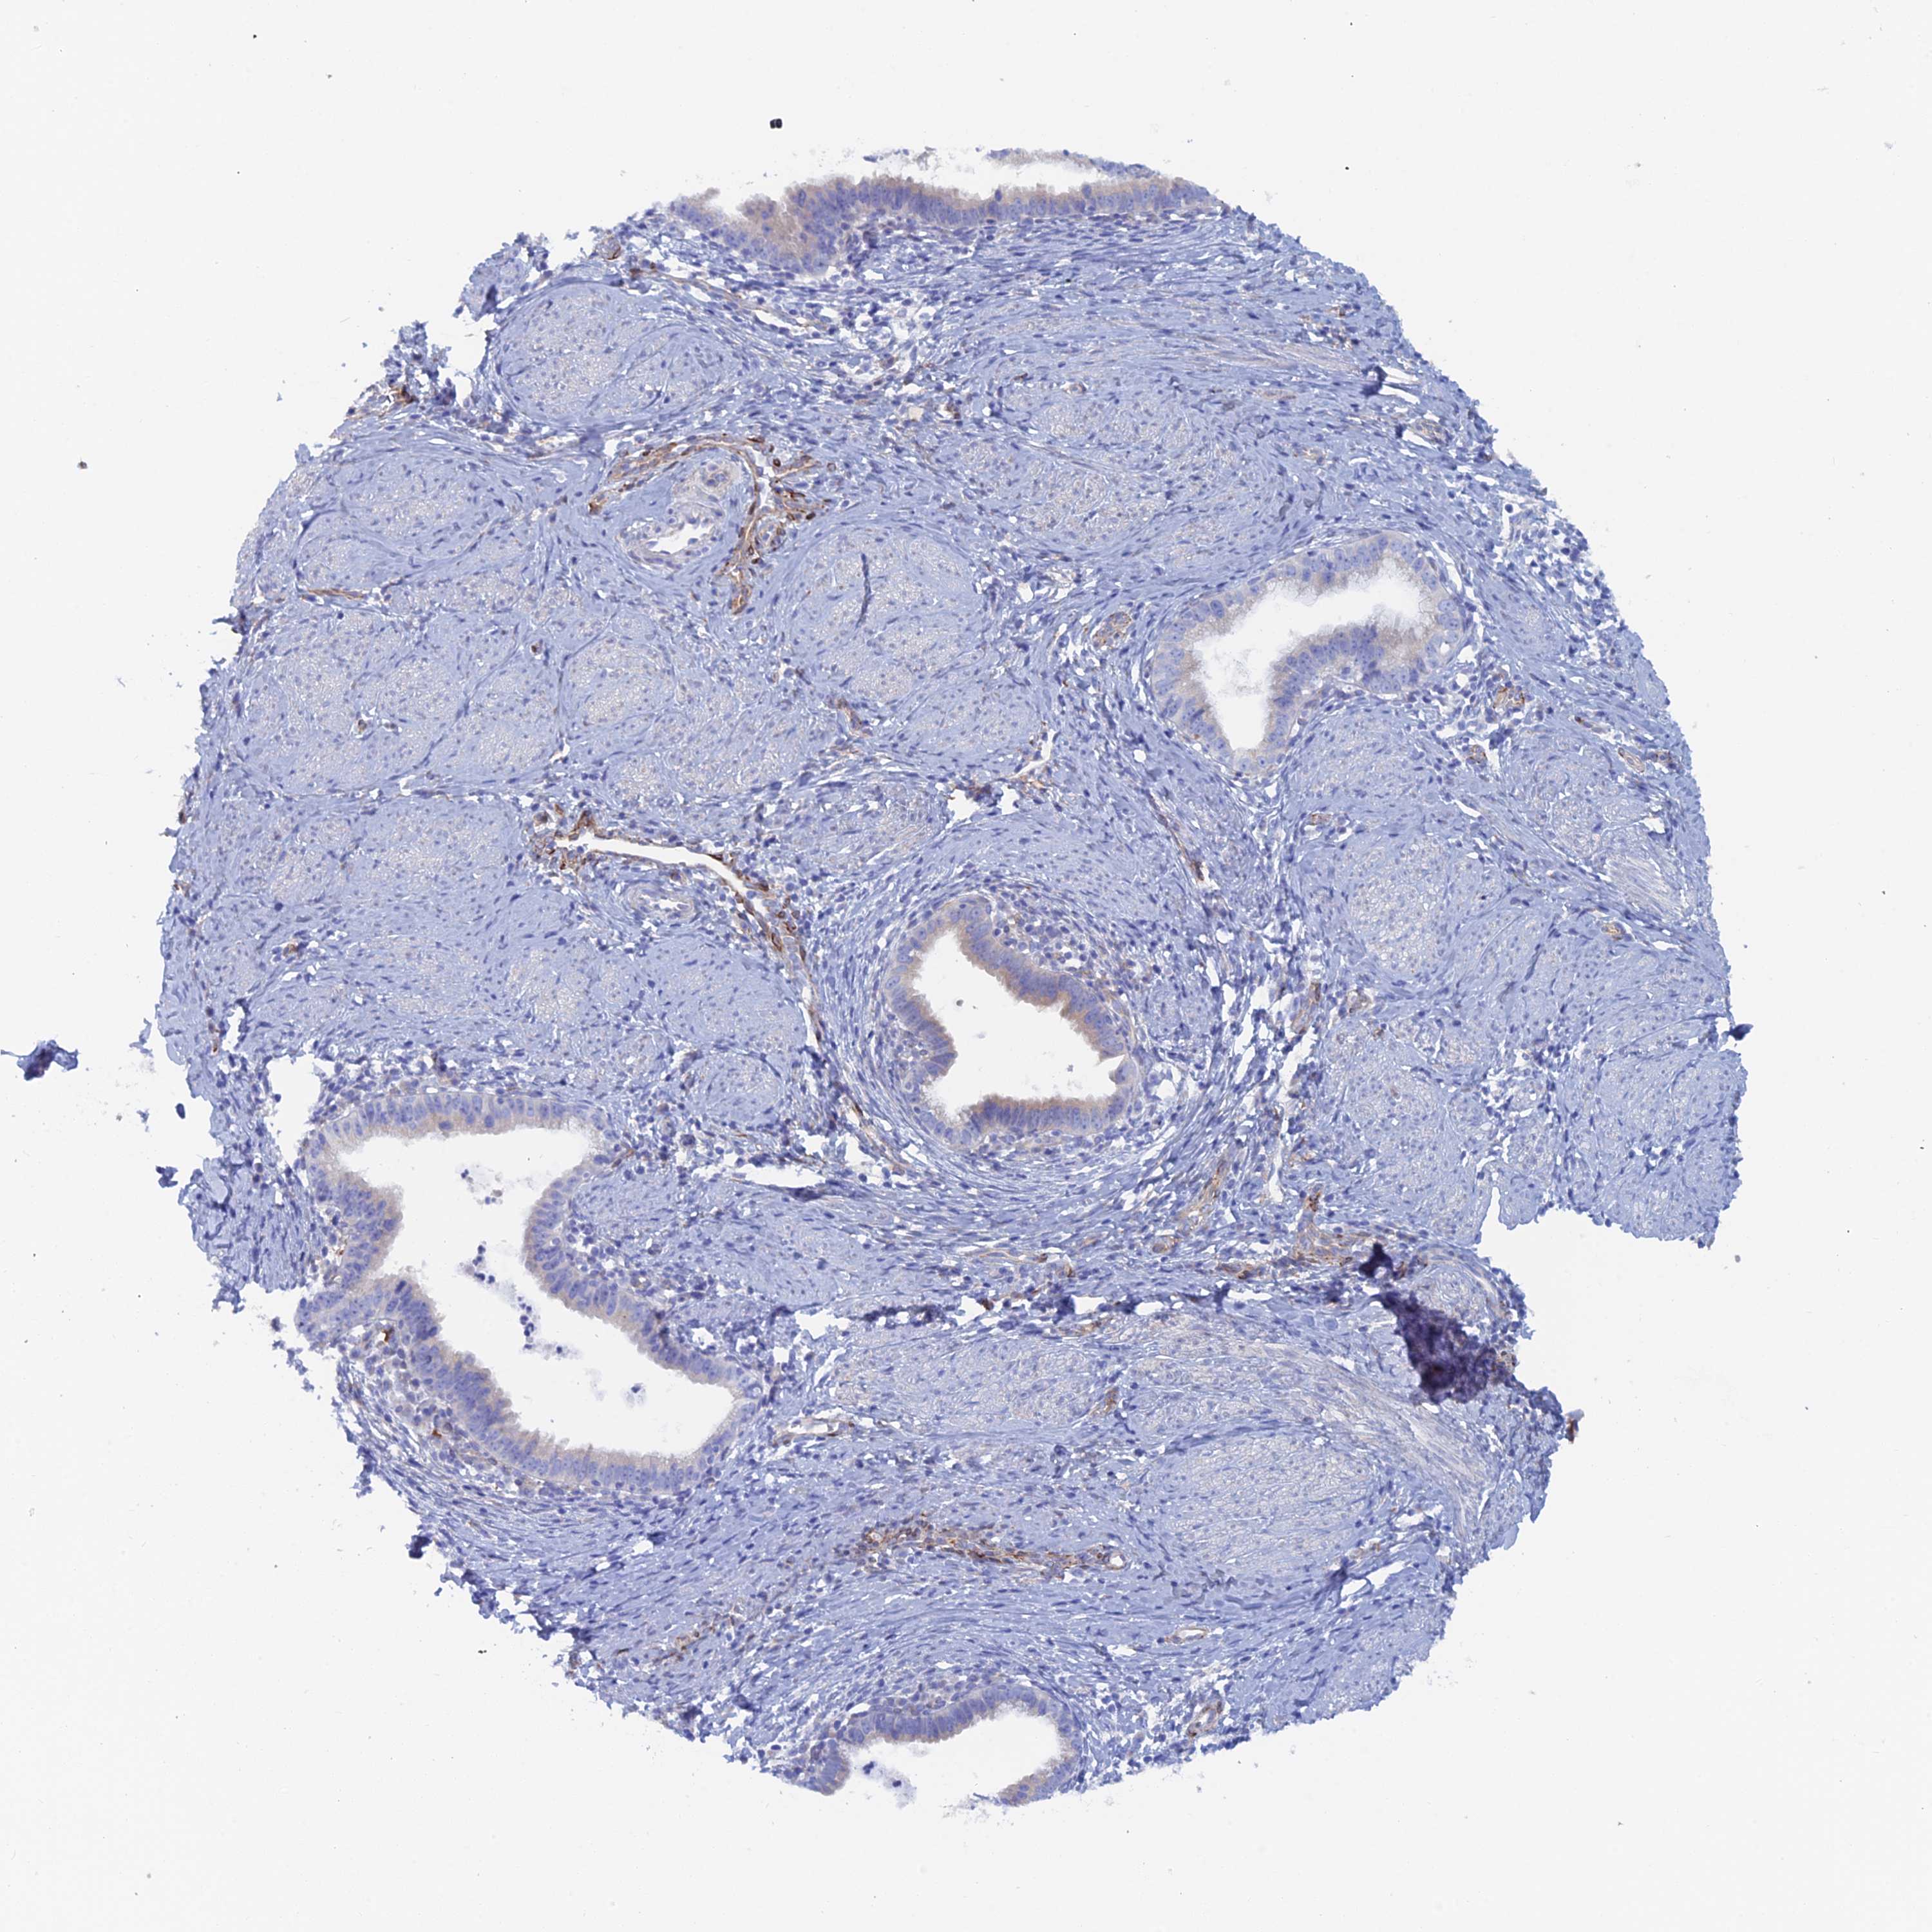

CERVICAL CANCER - Protein expressioni

A mouse-over function shows sample information and annotation data. Click on an image to view it in a full screen mode. Samples can be filtered based on level of antibody staining by selecting one or several of the following categories: high, medium, low and not detected. The assay and annotation is described here.

Note that samples used for immunohistochemistry by the Human Protein Atlas do not correspond to samples in the TCGA dataset.

Antibody stainingi

Antibody staining in the annotated cell types in the current human tissue is reported as not detected, low, medium, or high, based on conventional immunohistochemistry profiling in selected tissues. This score is based on the combination of the staining intensity and fraction of stained cells.

Each image is clickable and will lead to virtual microscopy that enables deeper exploration of all samples and also displays staining intensity scores, fraction scores and subcellular localization as well as patient and tissue information for each sample.

Antibody HPA040758

Staining

High

Medium

Low

Not detected

Intensity

Strong

Moderate

Weak

Negative

Quantity

>75%

75%-25%

<25%

None

Location

Nuclear

Cytoplasmic/membranous

Cytoplasmic/membranous,nuclear

Squamous cell carcinoma, NOS

Adenocarcinoma, NOS